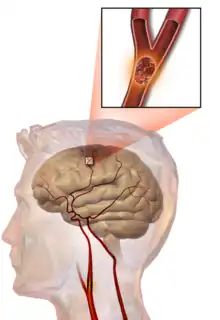

Embolic stroke

An embolic stroke refers to an arterial embolism (a blockage of an artery) by an embolus, a traveling particle or debris in the arterial bloodstream originating from elsewhere. An embolus is most frequently a thrombus, but it can also be a number of other substances including fat (e.g., from bone marrow in a broken bone), air, cancer cells or clumps of bacteria (usually from infectious endocarditis).[45]

Because an embolus arises from elsewhere, local therapy solves the problem only temporarily. Thus, the source of the embolus must be identified. Because the embolic blockage is sudden in onset, symptoms usually are maximal at the start. Also, symptoms may be transient as the embolus is partially resorbed and moves to a different location or dissipates altogether.

Emboli most commonly arise from the heart (especially in atrial fibrillation) but may originate from elsewhere in the arterial tree. In paradoxical embolism, a deep vein thrombosis embolizes through an atrial or ventricular septal defect in the heart into the brain.[45]